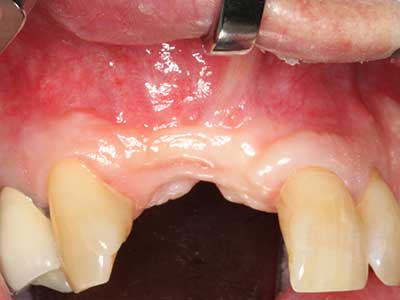

El tejido óseo no solo tiene un contenido puramente mineral, sino que también presenta una importante proporción de fibras de colágeno. Esto no solo garantiza una buena resistencia a la presión, sino también una cierta flexibilidad, que puede aprovecharse para la realización de aumentos. En la plastia de expansión clásica a efectos de una partición ósea, la cresta maxilar atrofiada se divide en su eje longitudinal y, tras alcanzar una profundidad de osteotomía suficiente, se extiende con cuidado (fig. 13-16), en un caso ideal sin desperiostizar de forma visible el maxilar (Brugnami, Caiazzo et al. 2014, Stricker, Fleiner et al. 2014). Los sistemas de tornillos y placas con distancia de expansión creciente han demostrado su eficacia para distanciar entre sí las dos tablas óseas por debajo del umbral de rotura. Por regla general, se requieren anchuras de hueso residual de al menos 3 a 4 mm (Chiapasco, Zaniboni et al. 2006) para garantizar una flexibilidad y una cobertura ósea suficientes de los implantes que van a incorporarse. En caso necesario, una osteotomía de descarga vertical unilateral o bilateral puede mejorar la flexibilidad. Como alternativa a la técnica clásica se ha descrito una combinación con otras técnicas de aumento, sobre todo en la parte bucal.

Con el uso de sierras piezoeléctricas la división se efectúa de forma especialmente cuidadosa y sin pérdidas importantes de las dimensiones, por lo que no se han encontrado diferencias significativas entre los implantes realizados en el maxilar dividido y en la cresta alveolar no deficitaria (Chiapasco, Zaniboni et al. 2006, Danza, Guidi et al. 2009). No obstante, precisamente en la partición profunda y limitada de forma local, es preciso asegurarse de que exista una adecuada irrigación por agua para evitar que se produzcan sobrecargas térmicas en las áreas de osteotomía apical.